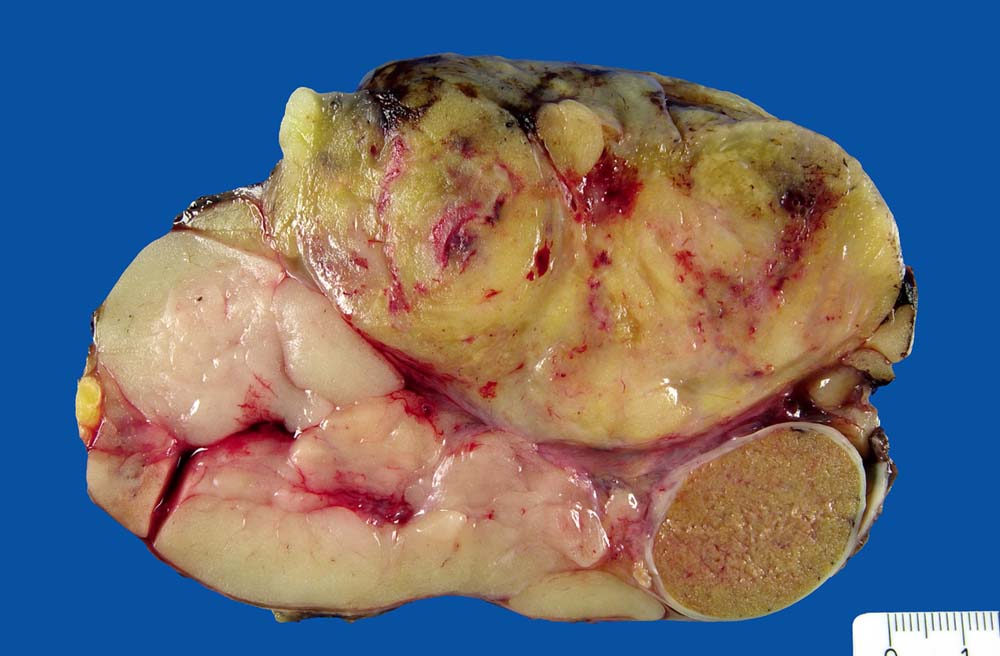

• Am rechten Rand des Präparates komprimierte Skelettmuskulatur.

• Links daran angrenzender scharf begrenzter Tumor mit reichlich myxoidem Stroma.

Makroskopie

Befund

Pathologischer Befund